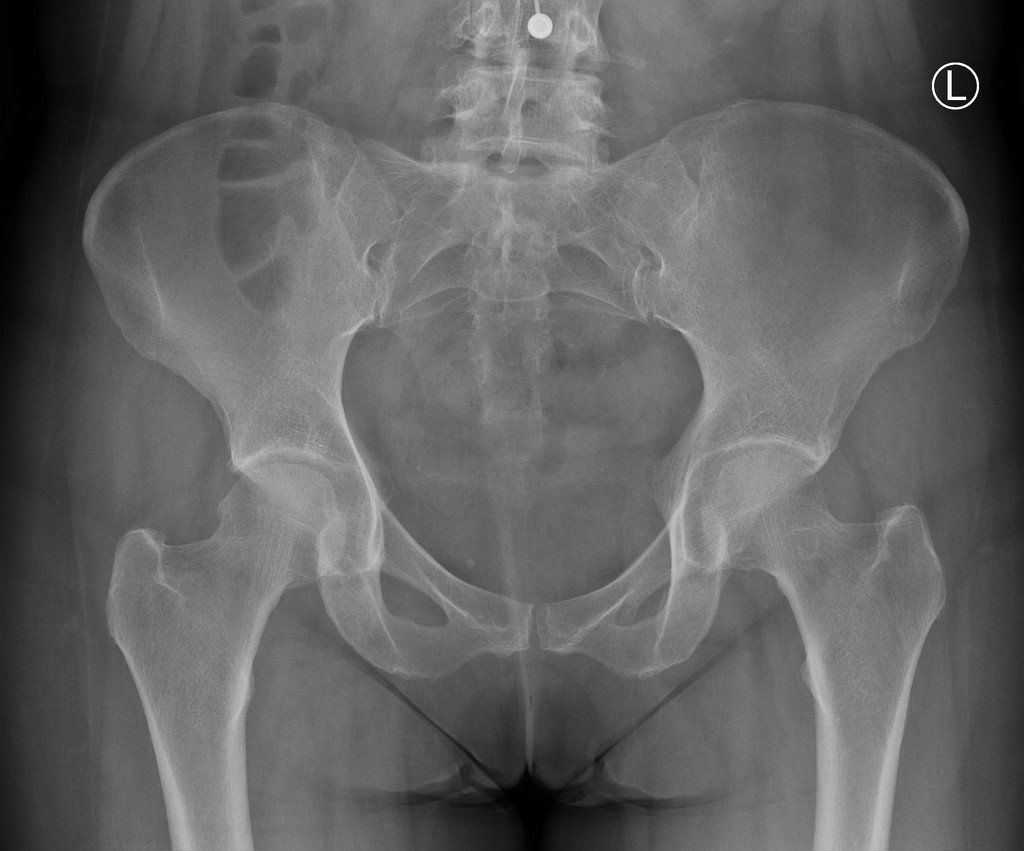

Diagnosis

Following a thorough understanding of the history and onset of your symptoms, movements of your lower back and hip will be assessed in an attempt to illicit your symptoms and also rule out any specific hip pathology. Palpation of the front of your hip where this specific nerve passes through may also illicit symptoms, confirming a diagnosis of MP.